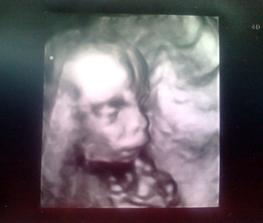

zlatinko moje ako sa mi máš? posielam vám všetkým cmuk.. a mám prekvapkoo.. už čoskoro sa vidíme 😀

@flamenga daujem....je cely tato :O) a ma aj naozajstny pipik :O)))))))))